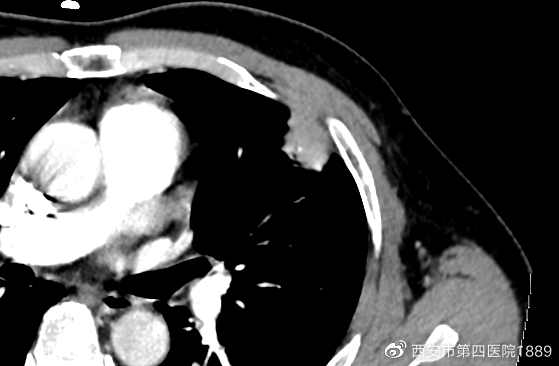

为了更好的了解病灶性质,需全方面观察结节形态、內部组织、血管关系等特点进行判断良恶性。通过CT图像后处理技术联合增强CT,得到病灶的多平面成像,进而从多个角度观察病灶特点,并观察病灶和血管的关系以及强化程度。

胸部增强ct三位重建,先后为矢状位及冠状位。

病灶增强图

通过多平面重建技术,先前右肺中叶在轴位呈现球星结节影,在矢状位及冠状位呈宽基底紧邻胸膜,未见明显胸膜增厚及牵拉,这是良性的表现。但是增强影像可见血管进入,需进一步观察病灶的内部情况。通过DWI(磁共振检查的一种方法)检查发现,患者双侧病灶ADC(抗体-药物结合物)呈高信号,证明该病灶为良性(炎症可能性大)。患者仅需口服莫西沙星1周,1月后复查胸部CT即可。